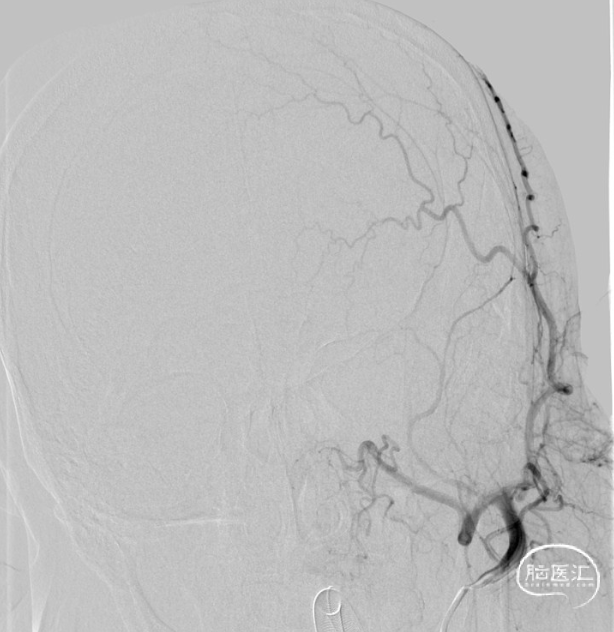

· 病例小结 ·

二期治疗